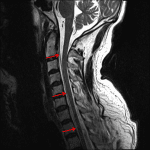

Indication: Trauma, no fracture on CT

Findings

- T2/STIR signal hyperintensity in the interspinous ligaments at C1-C2 and C2-C3 extending into the supraspinous ligament

- T2/STIR signal hyperintensity in the facet joints on the right from C2-C3 through C6-C7

- T1 isointense, T2/STIR hyperintense ventral epidural collection spanning C1-T1, measuring up to 5 mm in thickness, which effaces the ventral CSF and contributes to multilevel spinal canal stenosis, moderate in severity at C3-C4

- Associated uplifting of the dura

- No definite discontinuity of the posterior longitudinal ligament

- Normal marrow signal and vertebral body alignment

- Normal cord signal

- Multilevel facet hypertrophy and uncovertebral spurring contribute to moderate neural foraminal stenosis on the left at C3-C4 and mild neural foraminal stenosis on the right at C3-C4 and on the left at C4-C5

Diagnosis

- Epidural hematoma, ligamentous injury

Ventral epidural hematoma spanning C1-T1 measuring up to 5 mm in thickness, which effaces the ventral CSF and contributes to multilevel spinal canal stenosis, moderate in severity at C3-C4.

Findings concerning for ligamentous injury involving the interspinous and supraspinous ligaments at C1-C2 and C2-C3.

No marrow edema to suggest an acute fracture that was occult on the preceding CT.

Normal cord signal.